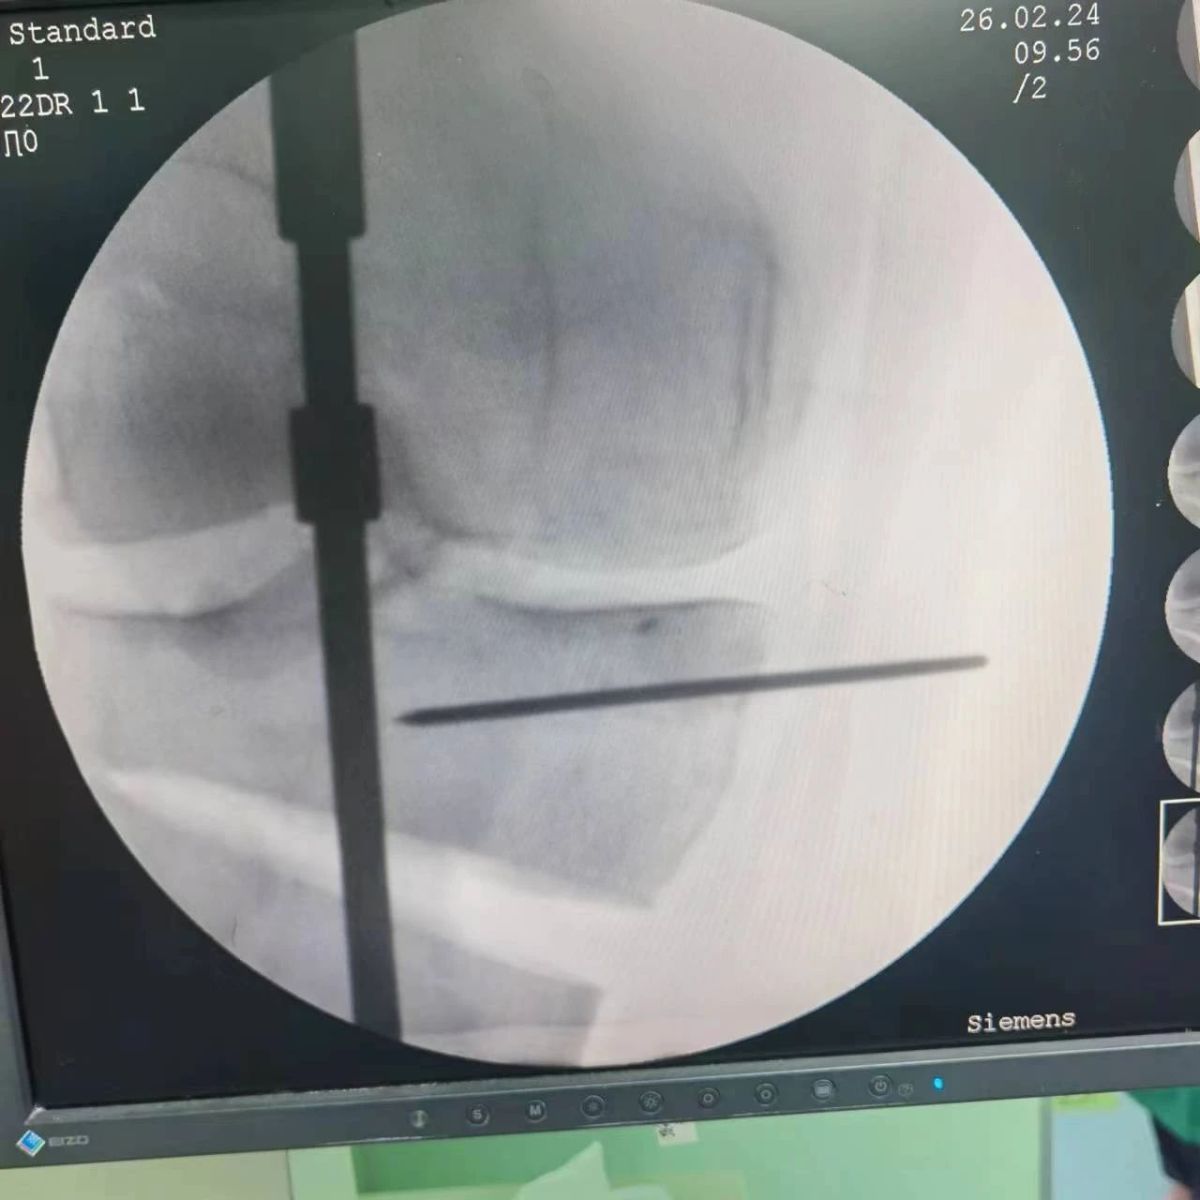

李付彬主任團(tuán)隊(duì)通過精準(zhǔn)術(shù)前規(guī)劃,設(shè)計(jì)目標(biāo)力線及調(diào)整撐開角度,轉(zhuǎn)化成需要撐開的高度,最終設(shè)計(jì)出同等高度的填充塊,術(shù)中驗(yàn)證力線調(diào)整與術(shù)前規(guī)劃完全一致!

鋼板位置、螺釘位置及長(zhǎng)度均可通過術(shù)前規(guī)劃計(jì)算,術(shù)中通過定位操作,基本與術(shù)前規(guī)劃一致,手術(shù)快速高效完成,外側(cè)合頁(yè)保留完整。無任何并發(fā)癥出現(xiàn)。術(shù)后見鋼板位置及力線糾正近乎完美!